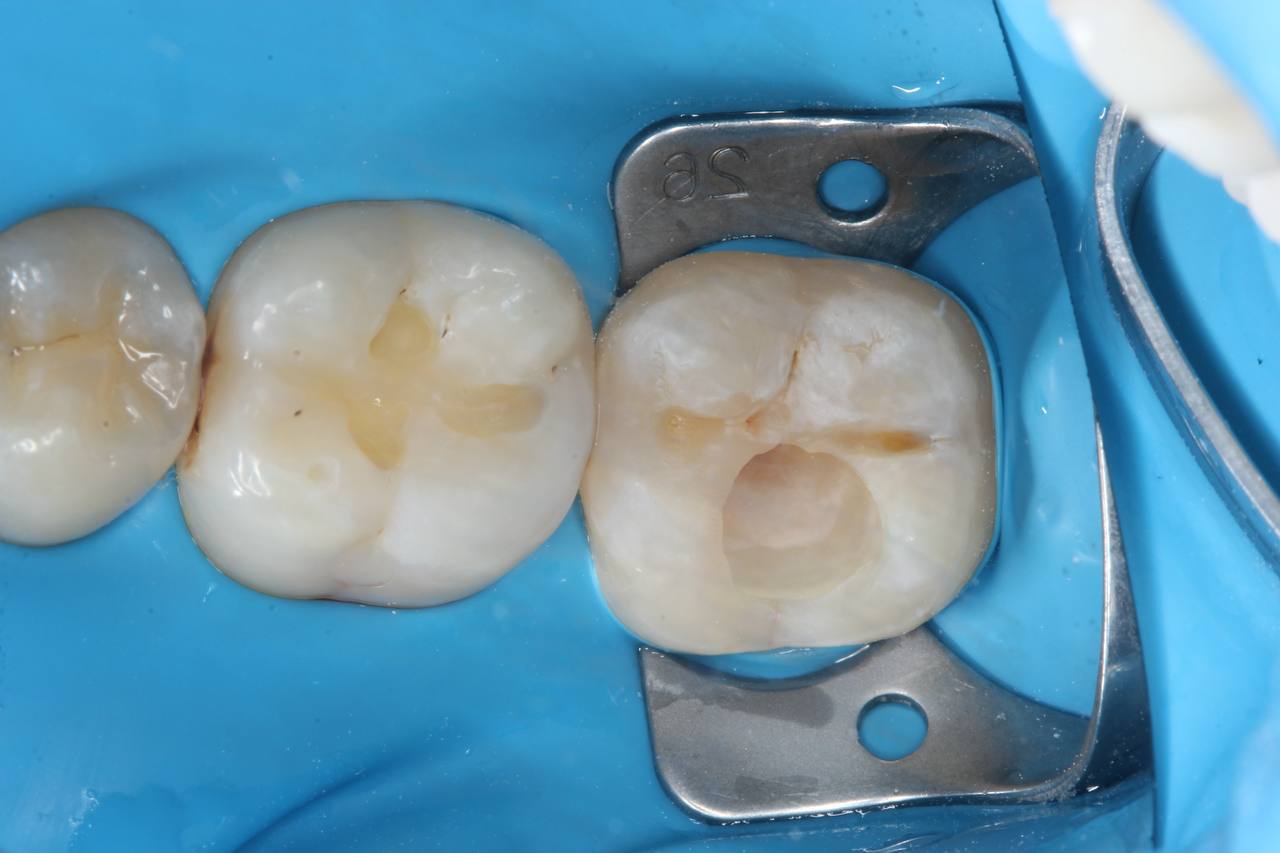

1. анестезия, препарирование кариозной полости

2. восстановление композитным материалом анатомической формы зуба

Результат

Здоровые, функциональные зубы